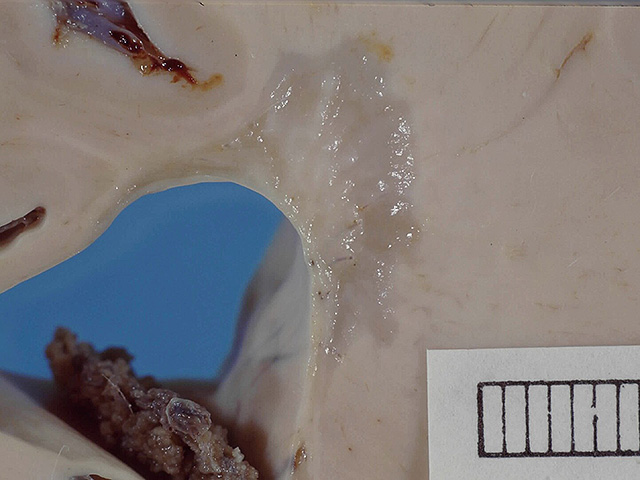

Данные по уровню sNfL и МРТ-изображения мозга были проанализированы с помощью модели машинного обучения SuStaIn. Как сообщается в журнале Brain, анализ позволил выделить два разных биологических варианта рассеянного склероза – "ранний sNfL" и "поздний sNfL". У пациентов с первым вариантом уже на начальных этапах болезни фиксировались повышенные показатели sNfL и повреждения в мозолистом теле, а очаги поражения в мозге появлялись и увеличивались быстрее. Ученые считают, что этот тип течения более активный и агрессивный. Во втором варианте сначала отмечалось уменьшение объема мозга – в частности, в лимбической коре и глубоких отделах серого вещества – и лишь затем возрастал уровень sNfL. Такое течение прогрессирует медленнее, а выраженные изменения проявляются позже.